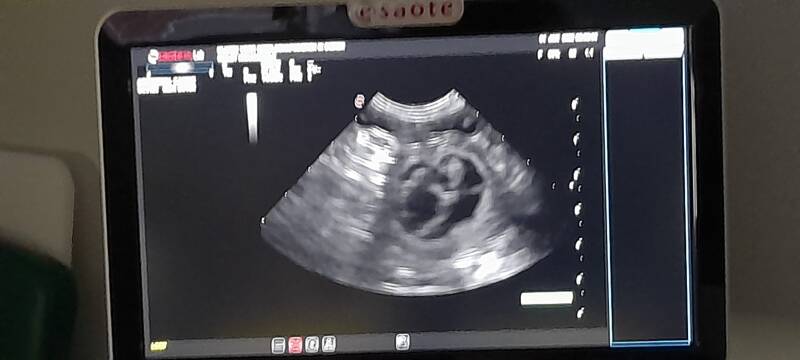

January 4, 2022.

Hopefully the year will start well and Hailey will be pregnant.

Really exciting, because in the weeks before you see things that you think she is pregnant, but it is always nice to have it confirmed.

We had the ultrasound early, so we quickly knew if she was pregnant,

When contact was made with the ultrasound machine you saw very quickly that she is pregnant. So nice to see that.

Awesome!!!! Hailey is going to be a mother!! We are so happy with it.

I am so looking forward to this litter.